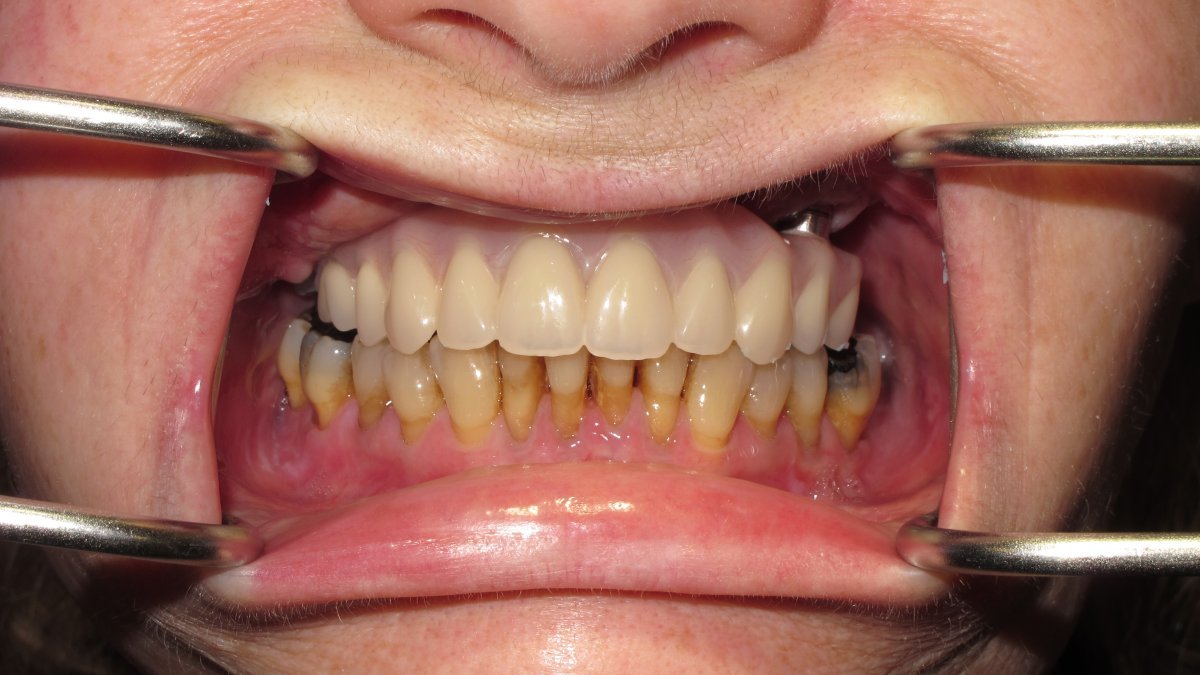

Fitted prosthesis